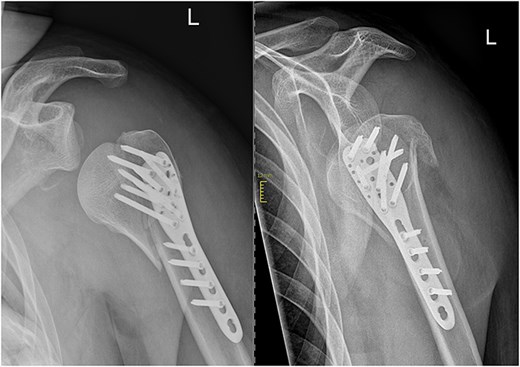

X-rays confirmed a dislocated 4-part proximal humerus fracture AO/OTA 11C3.1. The computer tomography scan demonstrated the presence of a Head-split component in the fracture (Fig. 1). Furthermore, it showed an anteroinferior dislocation of a larger articular surface-bearing fragment and avulsion of the greater tubercle. Neurological examination was intensified to ensure that the recent-onset epileptic seizure had not caused any neurological complications.

Open reduction and internal fixation with a locking plate was performed the following day. Following the deltopectoral approach, a reduction of the antero-inferiorly dislocated fragment through Kocher maneuvers and traction on the head fragment using a pointed reduction forceps were achieved. Subsequently, the head-split component was addressed by securing it with Ethibond sutures within the rotator cuff. The remaining fragments were then reduced and stabilized using a 5-hole anatomical locking compression plate along with a total of eight head and seven shaft screws, all performed under radiological guidance (Fig. 2).